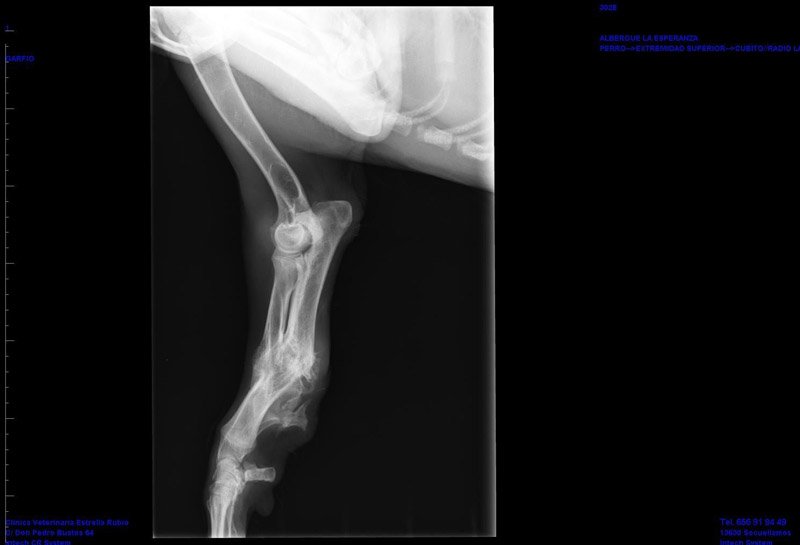

Garfio wurde auf einem Feld gefunden, wo er nach Futter und Wasser suchte. Er hat keinen Chip und niemanden, der ihn vermisste. Der junge, liebevolle Rüde hatte vermutlich als Welpe einen Unfall bei dem er sich sein Vorderbein gebrochen hat. Es ist etwas schief wieder zusammengewachsen, aber Garfio kann damit laufen und spielen wie jeder andere. Es muss sehr schmerzhaft für ihn gewesen sein, aber heute hat er keine Probleme mehr damit. Man mag sich das gar nicht vorstellen, ein noch so junger Hund erlebt so etwas schlimmes und niemand hilft, bringt ihn zum Tierarzt oder kümmert sich um ihn. Garfio sucht eine liebevolle Familie, denen sein kleiner Schönheitsfehler nicht stört und die ihn auch damit lieb haben, denn das hat der liebe und sehr menschenbezogene Strubbelrüde sehr verdient.